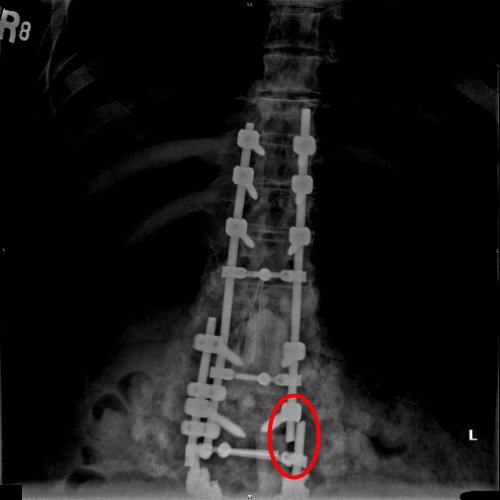

So we once again find our self in the same position we have been in twice over the past year. Through the x-rays we found that Joey had somehow broken the rods placed in his back during the last round of surgeries. In the pics below the broken rods are circled in red.

We have no idea how this could have happened. Joey had not done anything other then basic daily things like getting dressed with my assistance, and getting in and out of bed also with my assistance. So back we go. Jefferson Hospital seemed to be our home away from home. By this time Joey was feeling a bit more comfortable at the hospital. Not happy, but not as bad as the first or even second round. We knew the drill, but this time there would be a bit of a twist. The surgeon took out the broken hardware, cleaned away any infection that was detected and began to rebuild his spine...again. Not only did the surgeon replace the rods that had broken, he also attached additional rods in between the two vertical rods to help with the stability of the entire thing.